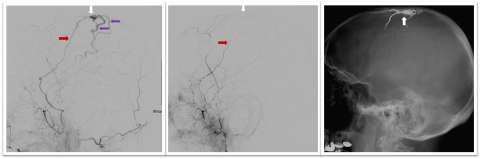

Figure 2. Dural Arteriovenous Fistula Embolization- Embolization of a DAVF accomplished by injected onyx, a glue-like liquid embolic material, into abnormal Middle Meningeal and Occipital artery branches.

• Endovascular liquid embolization: This minimally invasive technique is performed by inserting a catheter through the groin (or other vessel), then injecting a liquid that solidifies in the blood vessel and cuts off blood flow to the fistula. The cerebrovascular team at UCLA is actively involved in research and testing of new liquid embolic treatments (Figures 1-2). This is the most common method of treating DAVF, and it is often curative.